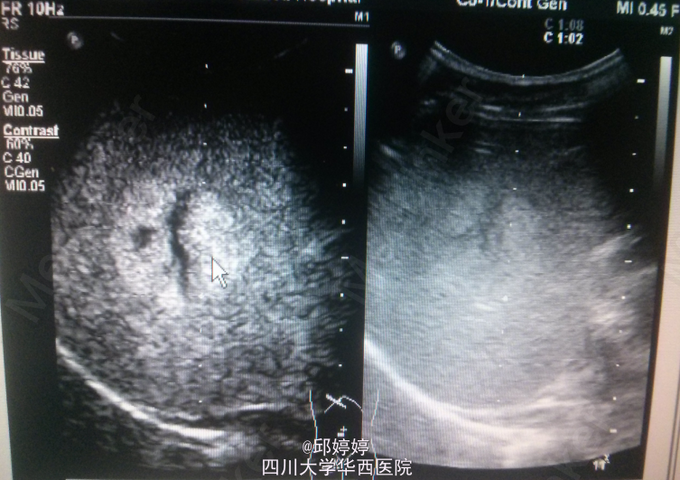

患者,男,36岁,体检超声发现肝内数个稍强回声团,较大位于右后叶,大小约5.0x3.7cm,上述团块边界清楚,形态较规则,较大者推挤右肝静脉,部分内部回声呈网格状;超声造影:团块动脉期呈环状结节样高增强(图1),门脉期持续向内充填(图2),实质期呈等增强(图3)。 讨论:血管瘤典型的超声造影表现特点明显,易于与其他良性或恶性病变相区分。